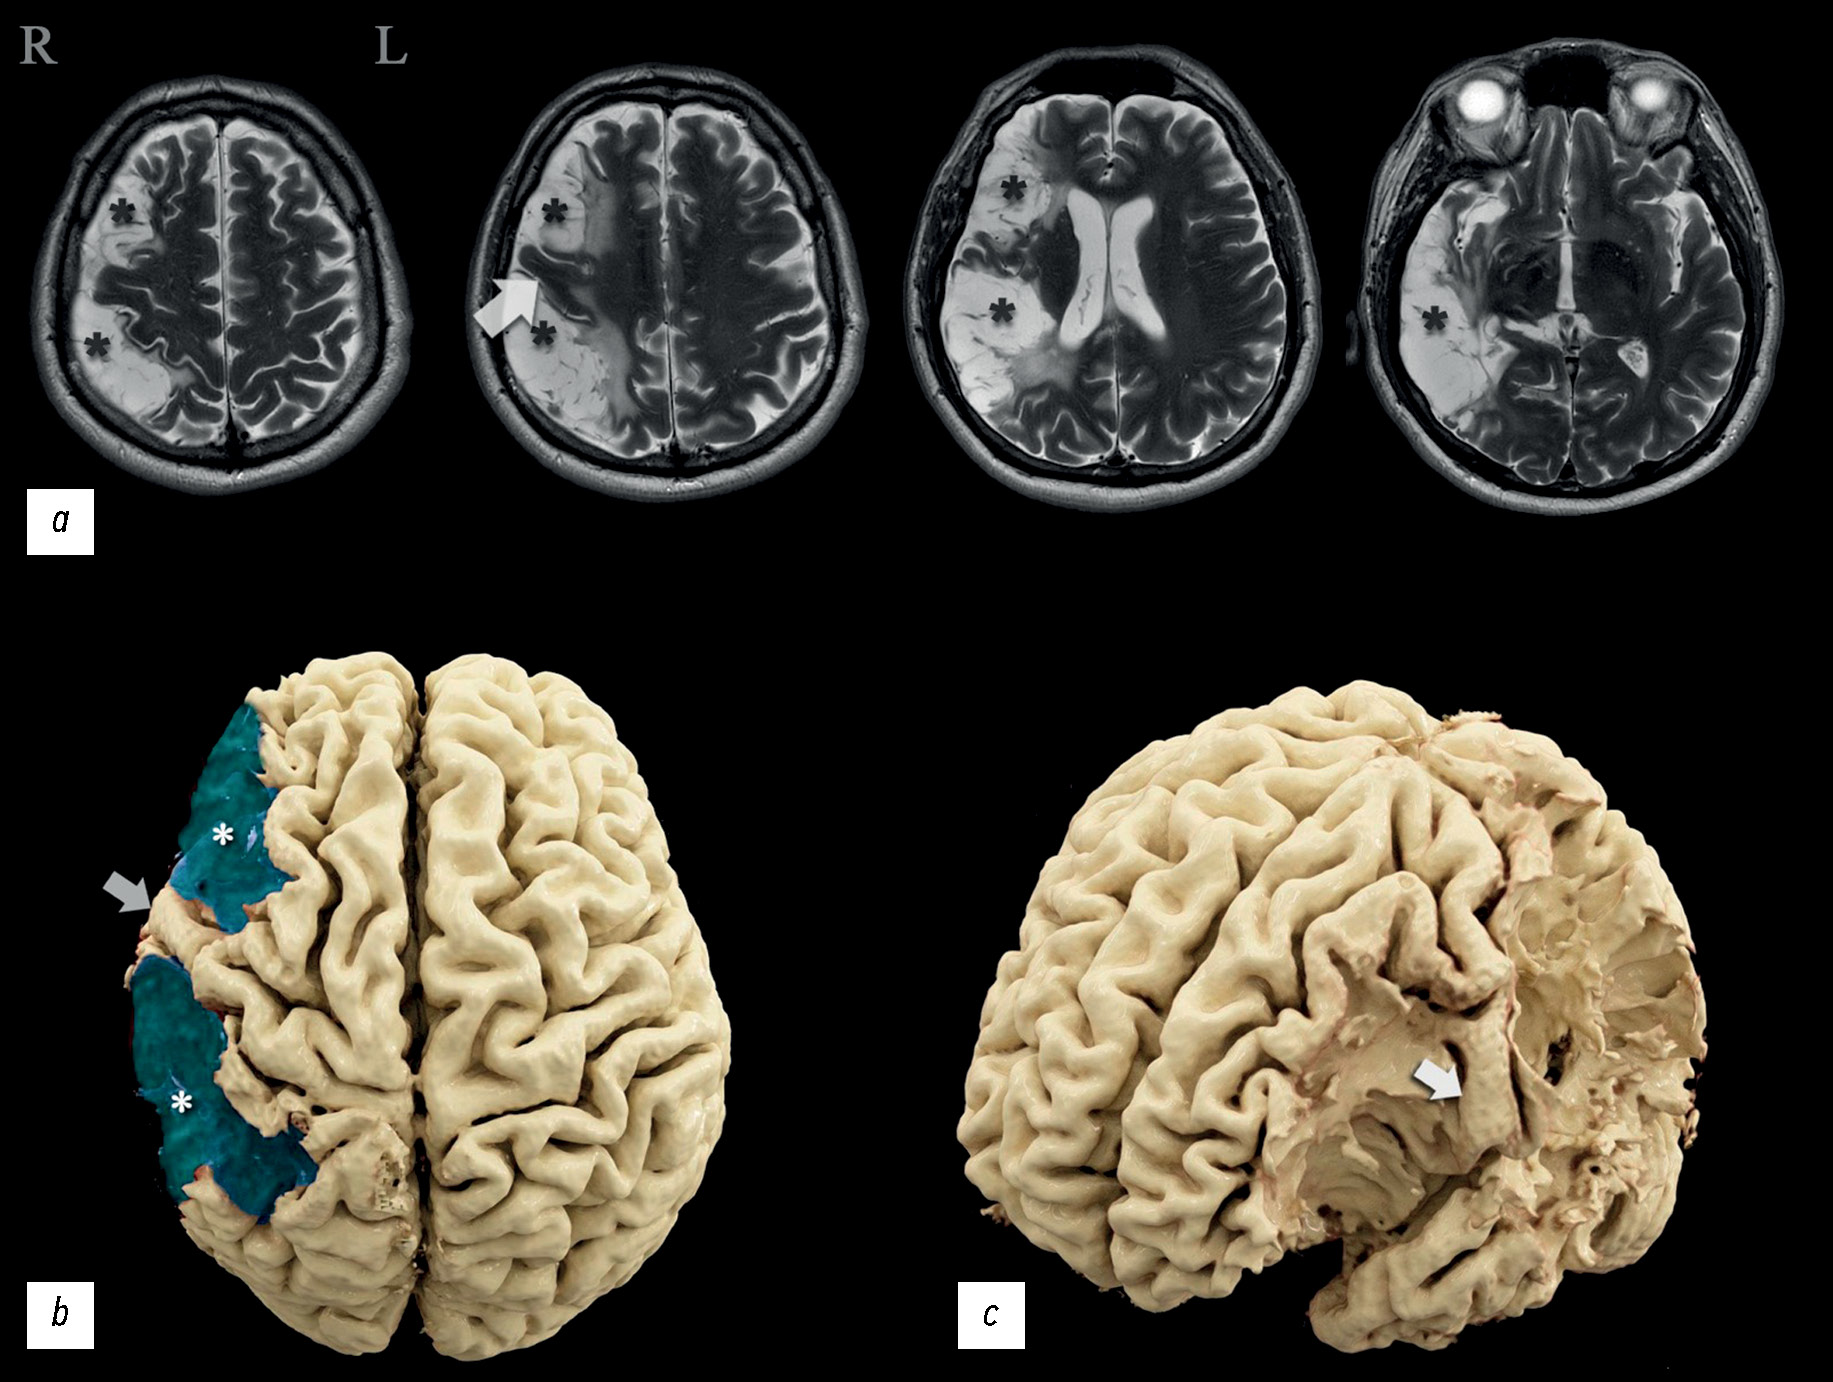

По результатам исследования были выявлены обширные зоны энцефаломаляции (рис. 1, *) в лобной, теменной и височной долях правого полушария, соответствующие бассейну правой средней мозговой артерии (СМА). На этом фоне отмечалась сохранность верхней лобной, медиальных отделов средней лобной и частично нижней лобной, прецентральной извилин (рис. 1, стрелка), с неполным сохранением передних отделов нижней, средней и верхней височных извилин; с субтотальным поражением ипсилатеральных теменной и височных долей, постцентральной извилины. Базальные ядра и кора островка, по данным МРТ, оказались интактны. По краю зоны энцефаломаляции отмечались признаки отложения гемосидерина. Визуализируемый правый желудочек был расширен за счёт отрицательного объёмного эффекта зоны кистозно-глиозных изменений.

Рис. 1. Магнитно-резонансные томограммы головного мозга и трёхмерные реконструкции по данным магнитно-резонансной томографии головного мозга: а — Т2-взвешенные томограммы в аксиальной плоскости; b — вид сверху (зоны кистозно-глиозных изменений — синим цветом); c — вид на область прецентральной извилины (зоны кистозно-глиозных изменений удалены); * — зона кистозно-глиозных изменений; стрелки — сохранная прецентральная извилина.